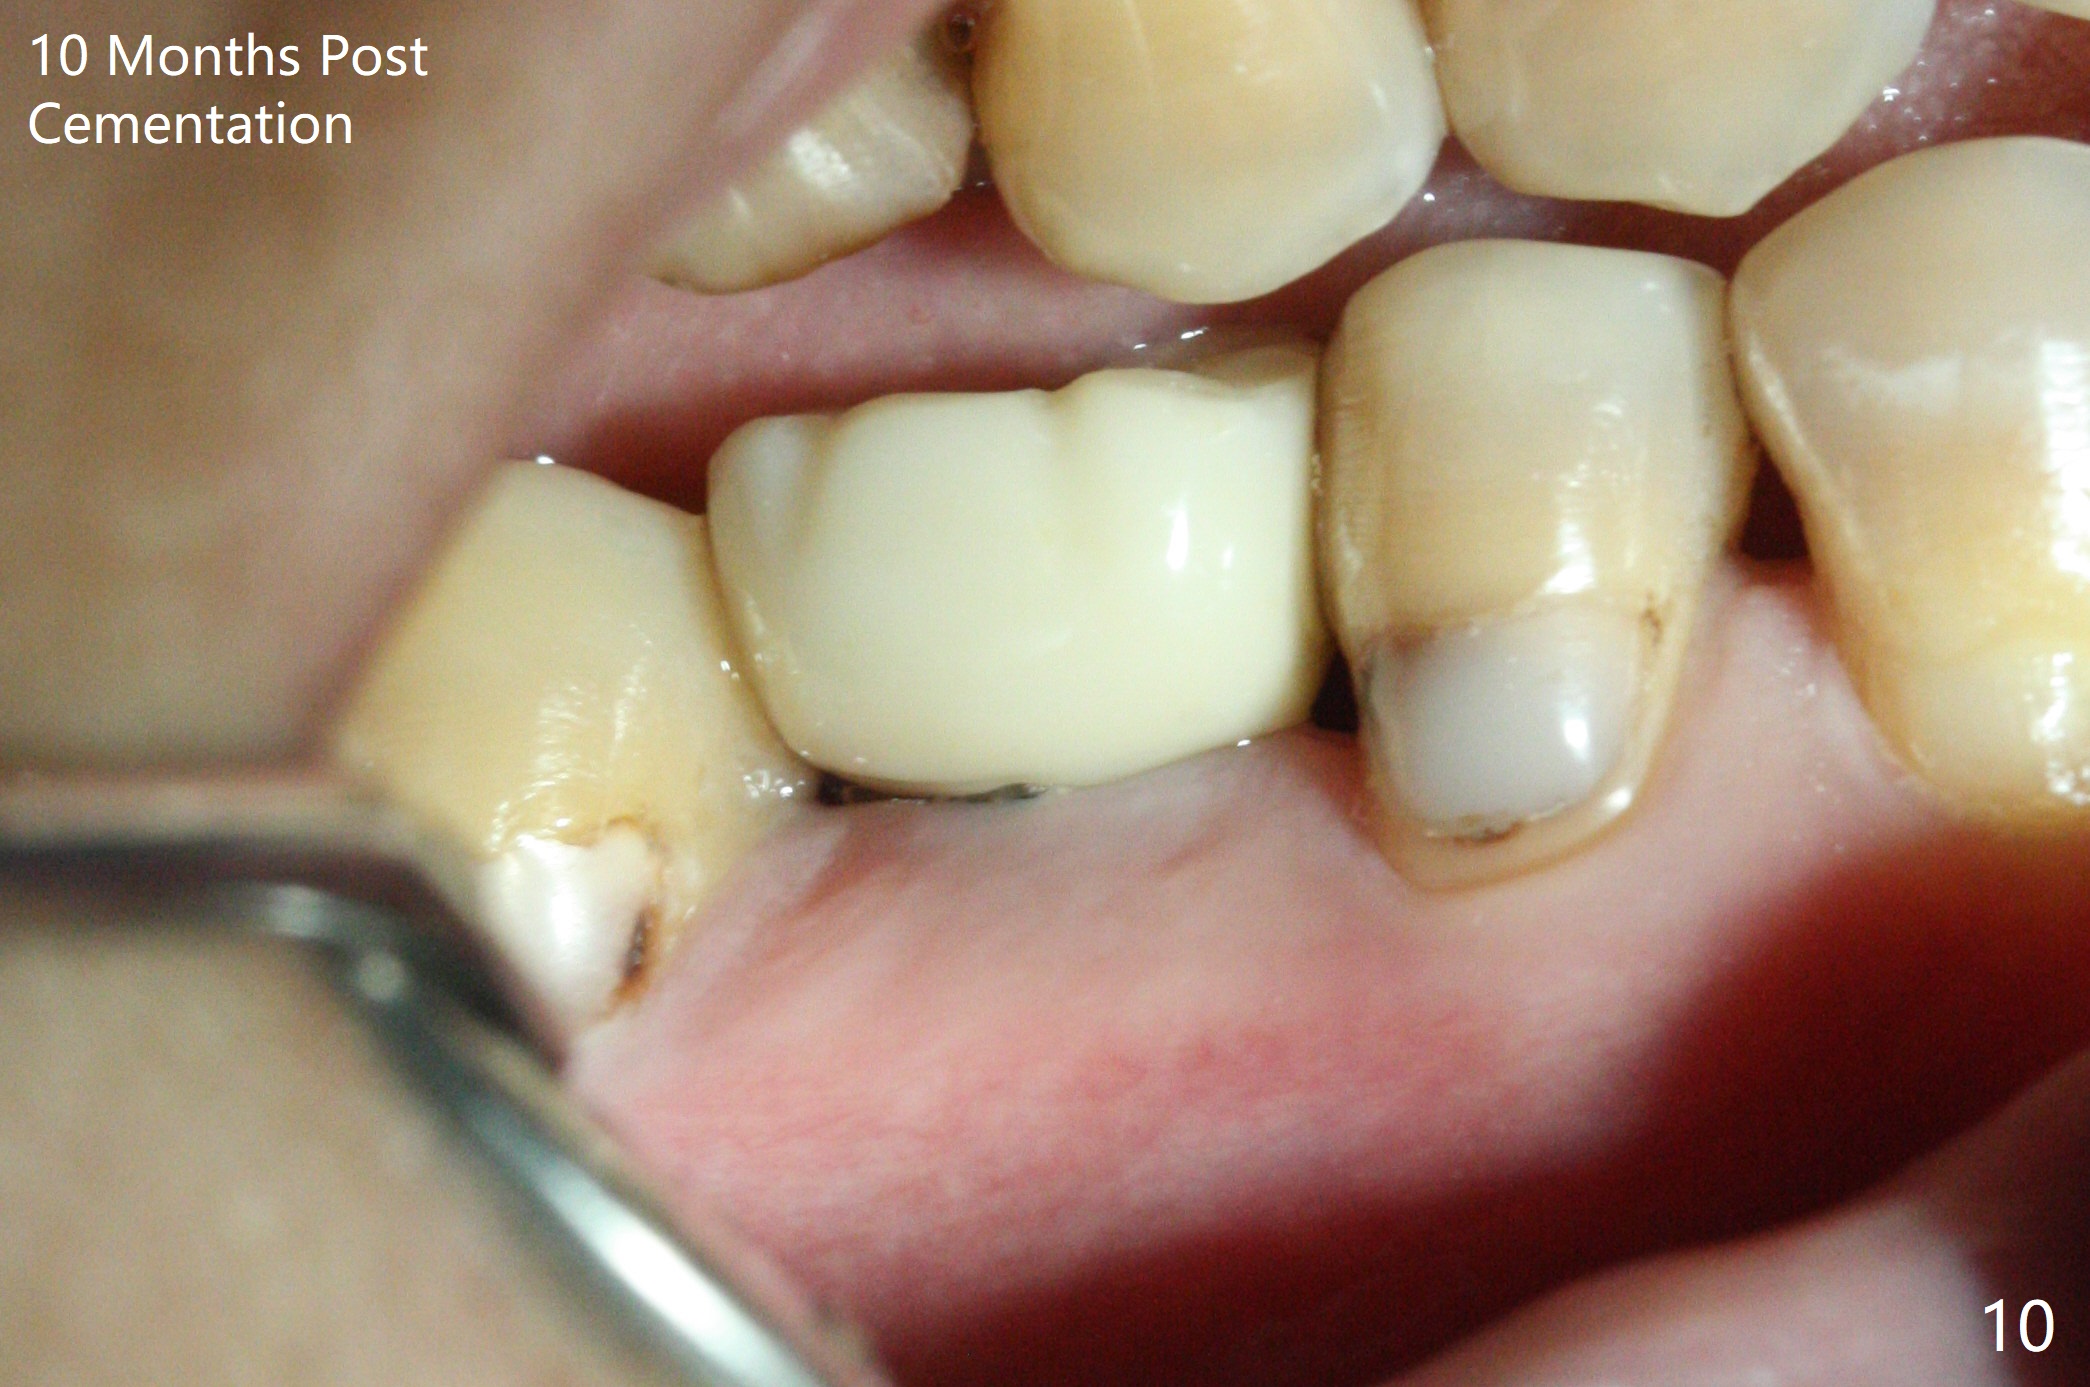

Before crown cementation, the ridge looks wider (Fig.7 *) than preop. There is no diastema between #31 and 32 (Fig.8, 17 days post cementation). The patient is pleased with less food impaction. The total treatment (including ortho) is 16 months. It appears that distalization of #29 is not effective to gain the bone width. In fact simultaneous GBR with implant placement is much more efficient. There is no bone loss 3 months post cementation (Fig.9). The gingiva looks healthy 10 months post cementation (Fig.10). The implant crown is functioning 1 year 9 months post cementation (Fig.11) and 3 years 7 months post cementation (Fig.12).